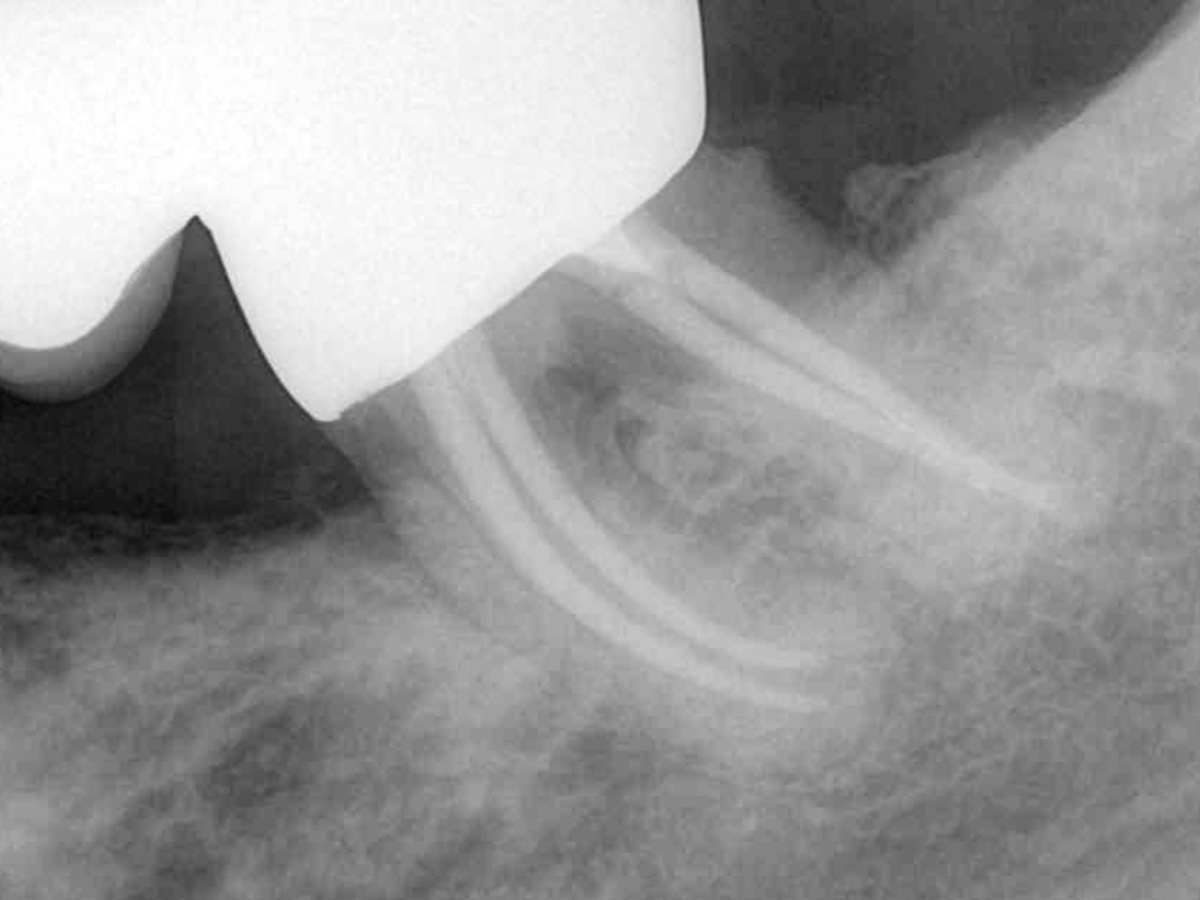

• Warm-VertikaleKondensation

• Kalt-Hydraulische Kondensation

• Vorhersagbare Wurzelfüllung bei unterschiedlichen Kanalkonfigurationen